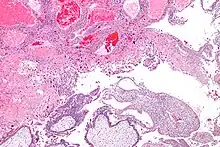

| Micrograph of intermediate trophoblast, decidua and a hydatidiform mole (bottom of image). H&E stain. | |